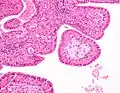

The appearance of this tumor under the microscope is unique. There are cystic spaces surrounded by two uniform rows of oncocytes, which are epithelial cells with abundant, granular, eosinophilic cytoplasm.[7] The cystic spaces have epithelium referred to as papillary infoldings that protrude into them. Additionally, the epithelium has lymphoid stroma with germinal center formation.

Low magnification micrograph of a Warthin tumor arising from the parotid gland. -

Histopathology of Warthin tumor in the parotid gland. H&E stain. -

Histopathology of Warthin tumor in the parotid gland. Another view of a file "Warthin tumor (1).jpg". H&E stain. -